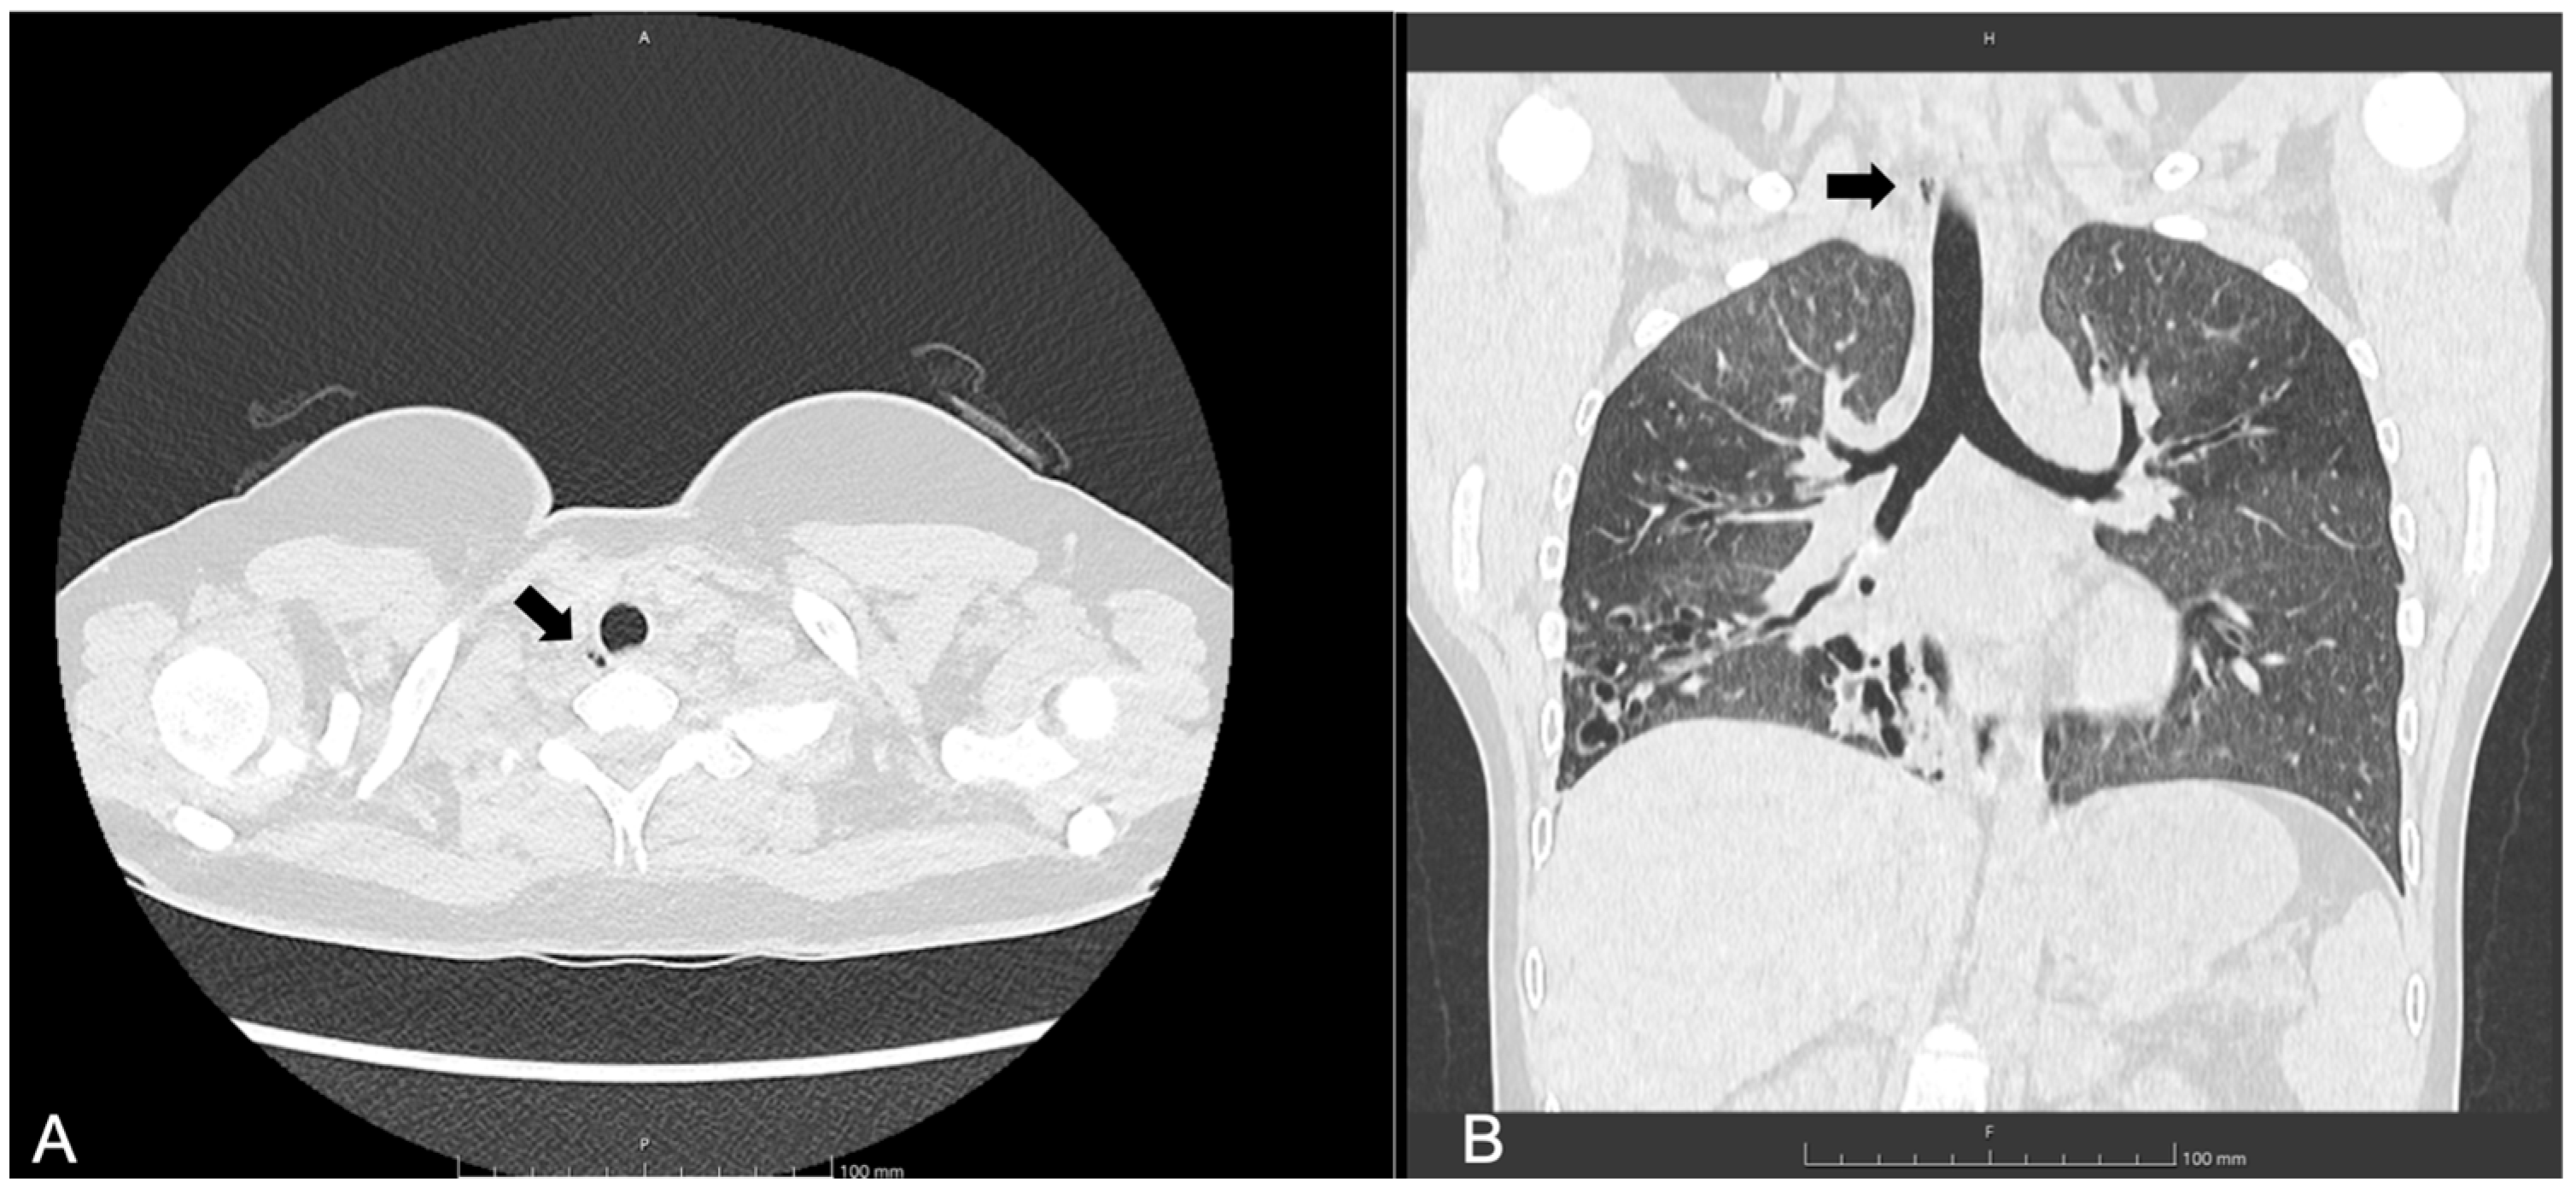

3.2. Patient 2

| 13, F | F508del/ Delexon22–24 | SA, PA | 63 | 12 | 1, right paratracheal at T2-T3 level | No | Not identified | MRI after 6 months: TD non reported |